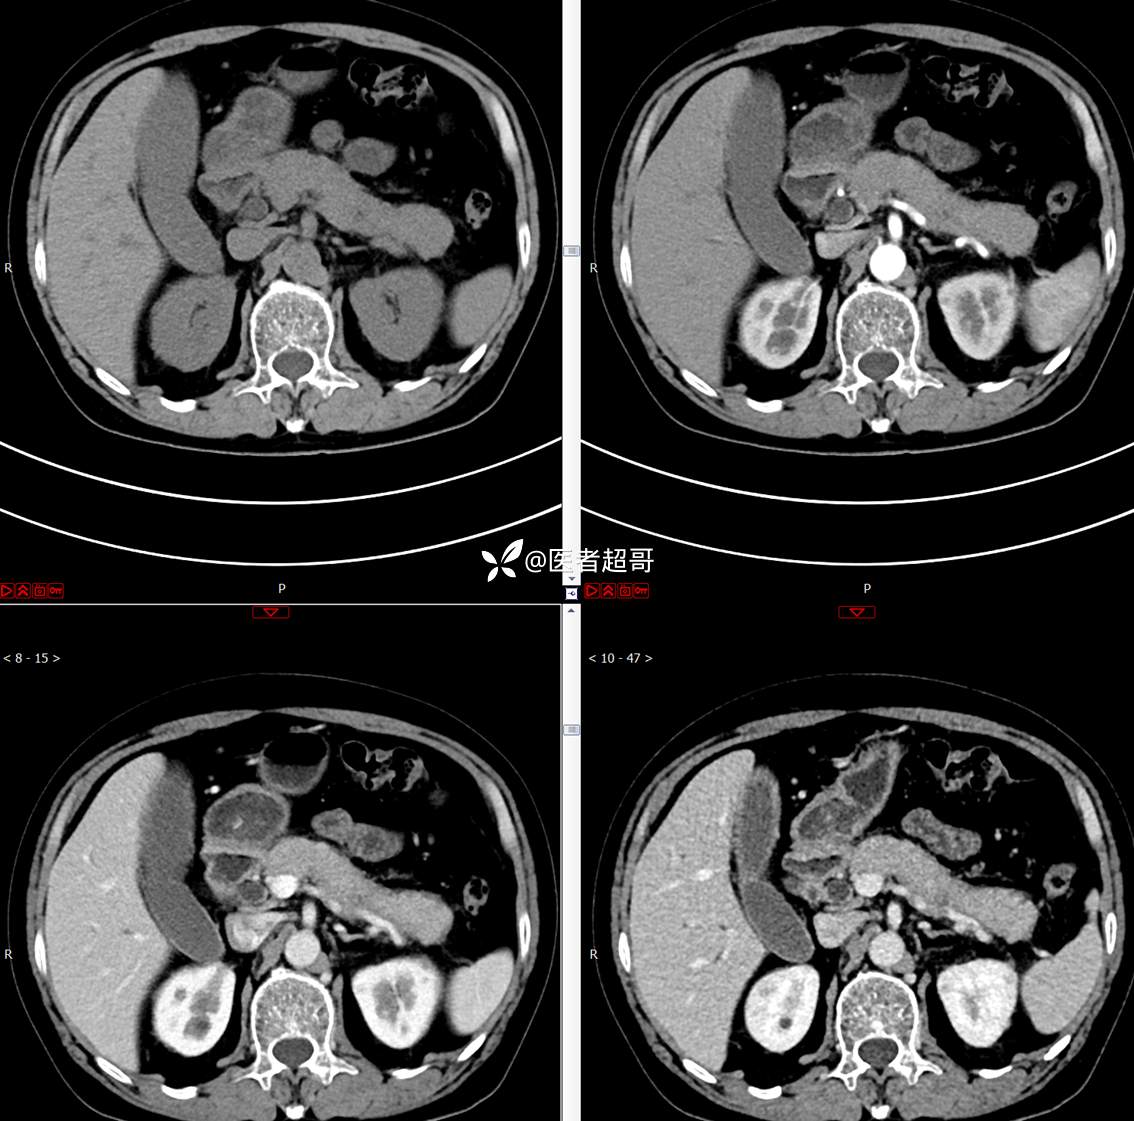

【影诊笔记772】腹痛就诊,发现肾脏病变,CT、MRI齐全,请高诊!

男,63岁 0200825 01

主 诉:间断腹痛15天

现病史:患者15天前无明显原因及诱因出现腹部疼痛不适,呈间断性钝痛,右下腹为著,无尿频、尿急、尿不尽,无发热、寒战,无腹胀。于市中心卫生院住院治疗,超声示:胰头低回声包块,胆系扩张,左肾囊肿,胆囊壁毛糙,胆囊内胆汁淤积。患者为求进一步诊治,遂以“肾盂肿瘤”收入院,患者自发病以来,神志清,精神可,饮食睡眠可,大便无明显异常,近期体重无明显增减。

既往史:既往体健